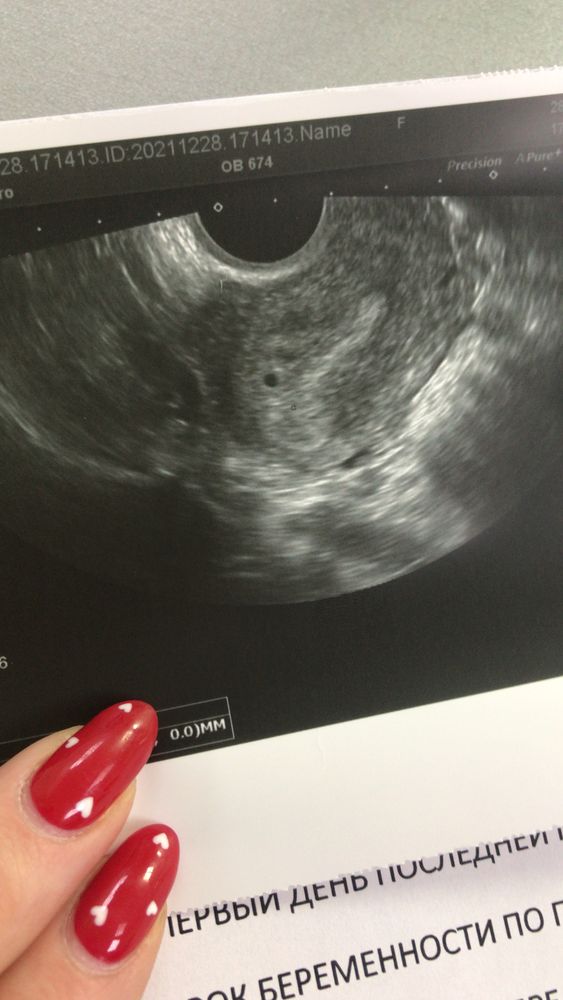

Девочки, норма ли это, акушерских 5 недель и 3 дня. Сходила убедиться, маточная ли, теперь чет переживаю😂

Врач еще такая «ну я не знаю чо это, какой то пузырь, может ПЯ, ну вроде да, оно»

Какой красивый колобочек😌❤️💜очень даже беременность, просто совсем кроха, вот подрастет через 1-2 недели и покажите этому узисту его (не знаю что это)😠

Да,все хорошо…видно же бусинку🥰😍